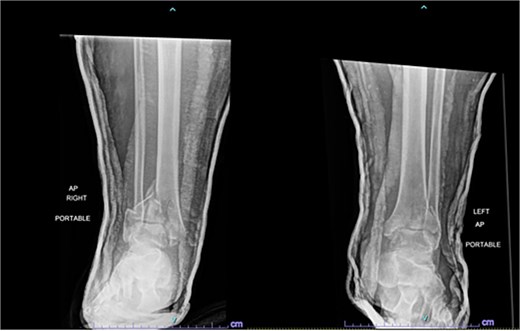

One year after the initial surgery, the left leg healed without any complications. However, the right leg developed nonunion through the distal tibia, along with posttraumatic arthritis. As a result, the patient underwent a right ankle fusion. Additionally, 2.5 years after the index surgery (1.5 years after the ankle fusion), the patient required removal of the right lateral fibular plate due to painful hardware. Six months later (3 years post-index surgery), the patient then underwent subtalar fusion due to post-traumatic arthropathy and ongoing pain (Fig. 2).

Radiographs of patient 1 obtained 3 years after the index procedure, including AP view of the left ankle and lateral and oblique views of the right ankle following subtalar fusion.